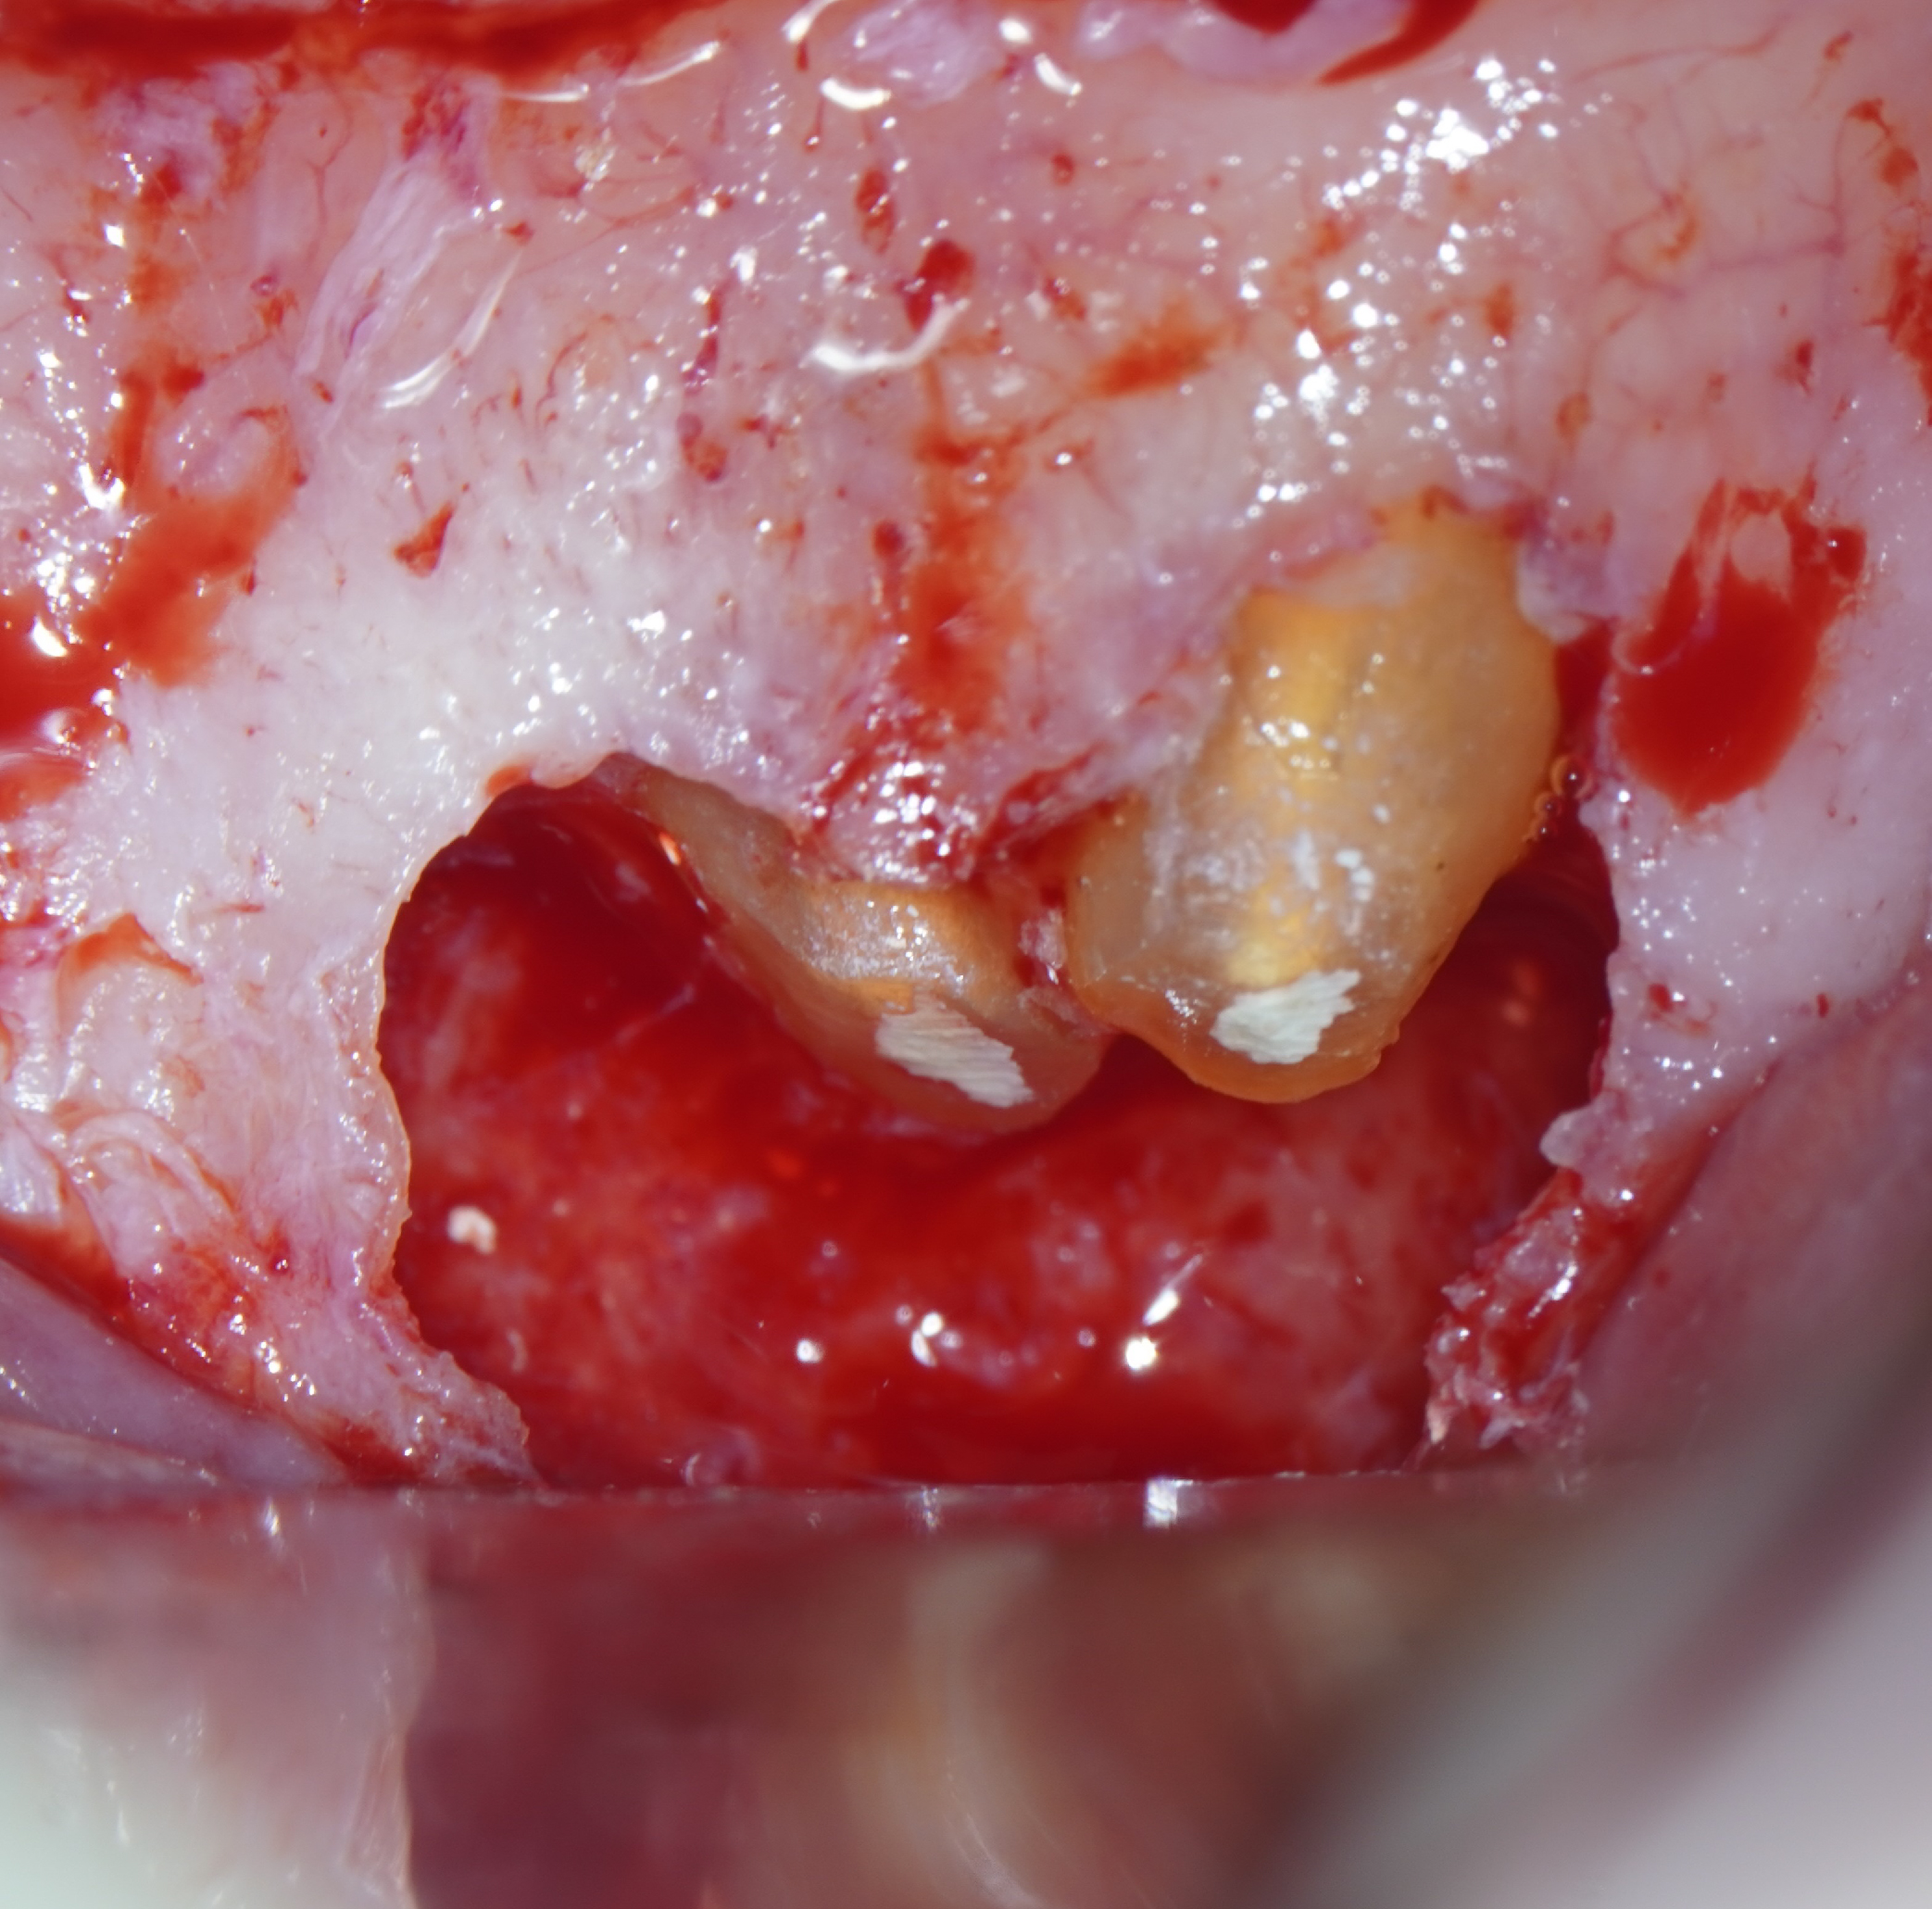

Imágenes del tratamiento

* Haz click sobre las imágenes para verlas a mayor tamaño y a color